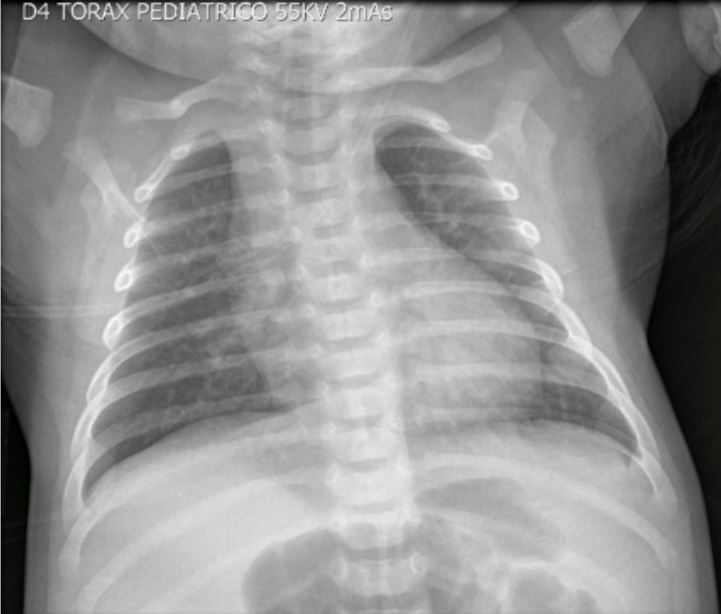

En el reingreso presentó signos de dificultad respiratoria, dados por aleteo nasal, retracciones intercostales y subcostales, hipoxemia y sibilancias a la auscultación pulmonar. La impresión diagnóstica fue de bronquiolitis (escala de Woods-Down-Ferrés = 4 puntos). Se inició oxígeno por cánula nasal y se hicieron lavados nasales. Se solicitaron exámenes paraclínicos de extensión: el panel viral de ingreso fue negativo, la radiografía de tórax mostró opacidades intersticiales de predominio parahiliar (figuras 1 y 2) y fueron negativos los hisopados rectales.